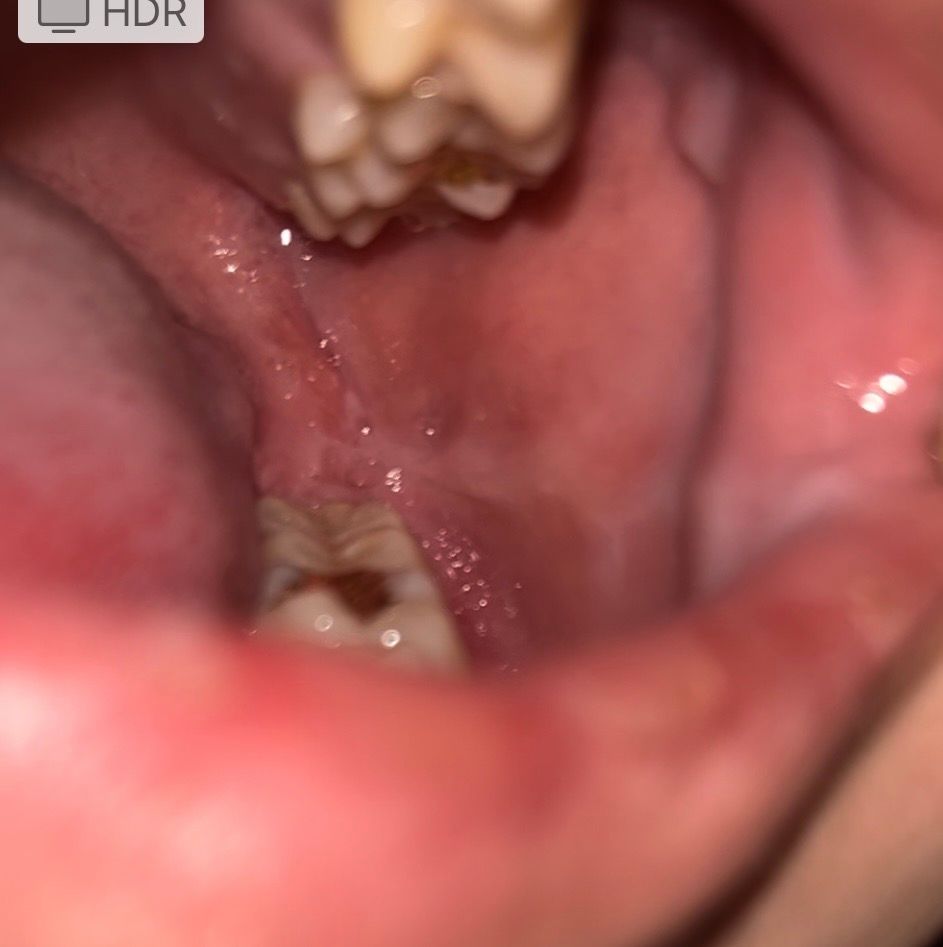

요즘 공부하느라 잠 많이 못 자서 그런지 아니면 깨물었던 건지 구내염이 생겼네요 찾아봤는데 편평태선 이라는 것도 있더라고요 혀 옆면에 붉은 반점 같은게 저렇게 있는데 맞나요? 뭐죠 저게ㅜ 어릴때부터 있었던 거 같아요 또 그냥 구강 상태 괜찮은건가요 20대 초반 흡연자입니다ㅜ 걱정되네요

• 2번 째 사진